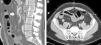

Abdominal CT scan showed a filling defect in the proximal segment of the SMA, suggestive of a thrombus that lead to stenosis of approximately 60%. There was also a linear defect inside the lumen of the vessel that extended to a jejunal branch, which may have corresponded with a flap associated with the dissection. Adequate distal filling was observed with no signs of intestinal ischemia.

Initially, we opted for a conservative approach with anticoagulant therapy (heparin). The progression of the patient's condition became torpid, with more pain and guarding in the right hemiabdomen. The leukocytosis continued, associated with neutrophilia and mild metabolic acidosis. Given the worsening symptoms, we decided to perform CT angiography, which showed evidence of a small repletion defect at the origin of the ileocolic artery, with distal opacification related with a partially occlusive thrombus. The ileal loops located in the iliac fossa and right flank presented intestinal suffering (Fig. 1). Given the hemodynamic stability, we decided to perform a radiological approach using arteriography of the SMA, where a dissection flap was observed within the first few centimeters, causing obstruction of all the ileal branches, with no evidence of stenosis at the origin (Fig. 2).